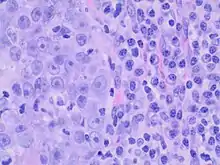

On histopathology, medullary breast carcinoma is characterized by groups of tumor cells with syncytial appearance (that is, seemingly fused cytoplasms, at left). There is typically also a lymphocytic and plasma cell infiltrate (right).[5]

Criteria must be met through the Ridolfi criteria. Although there are other classifications for diagnosis, the Ridolfi criteria are the most commonly used. There must be histologic evidence of lymphoplasmacytic infiltration, noninvasive microscopic circumscription, greater than 75% syncytial growth pattern, and high-grade nuclei.[5] It is immunologically typically triple-negative, with negative estrogen receptors (ER), negative progesterone receptors (PR), and negative HER2/neu receptors.[3] There are also medullary breast carcinomas that are found to be estrogen receptors (ER) and/or progesterone receptor (PR) positive, making diagnosis less straightforward.